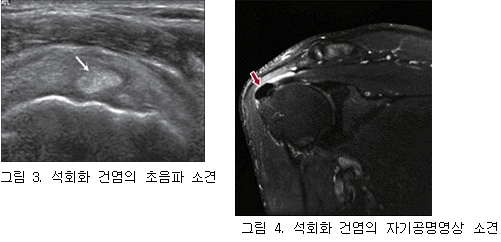

출처: 대한류마티스학회

출처: 대한류마티스학회 석회화 건염은 앞에서 설명한 특징적인 급성 통증 증상 및

영상검사(방사선, 초음파, MRI)를 토대로 진단합니다.